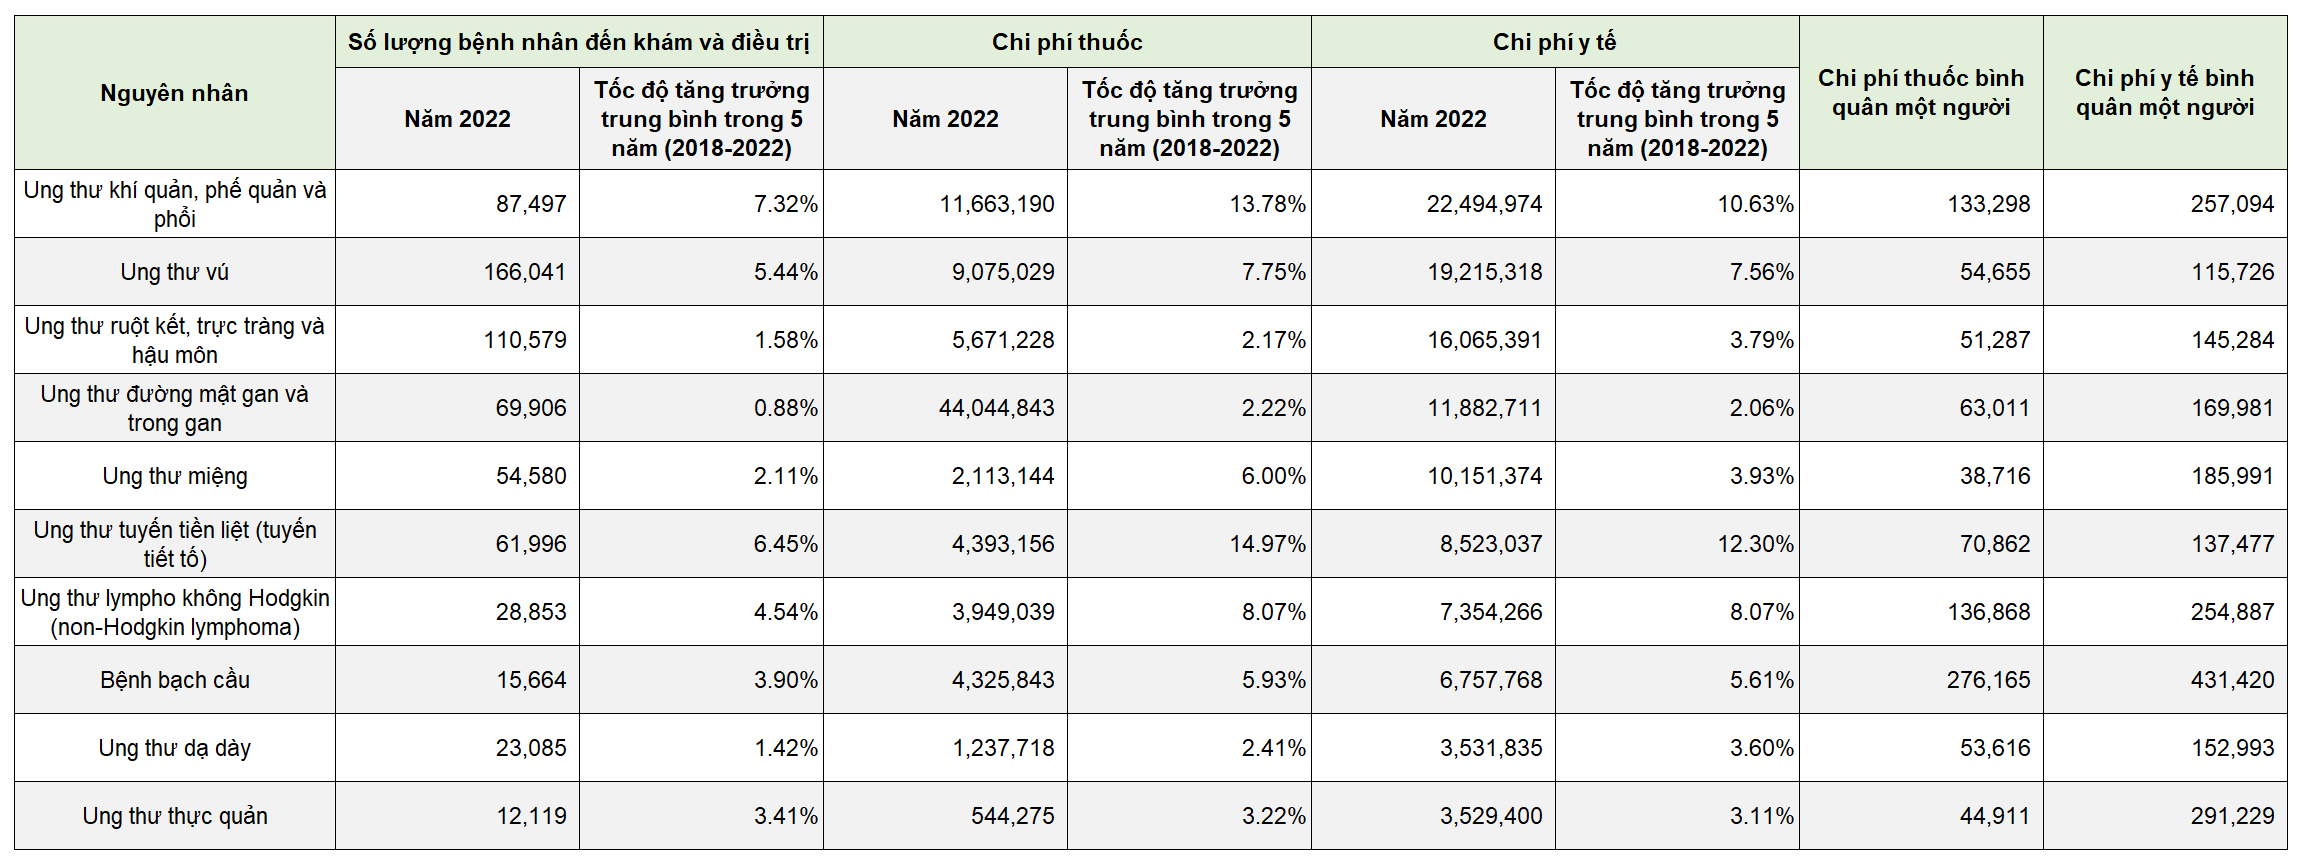

Bảo hiểm y tế quốc gia cho khối u ác tính năm 2022

Thống kê chi tiêu y tế cho 10 bệnh ung thư hàng đầu

- Trong 5 năm qua: số người tìm đến điều trị y tế cho bệnh ung thư phổi đã tăng từ 61.000 người vào năm 2017 lên 87.000 người vào năm 2022. Những con số đáng kinh ngạc này nhắc nhở chúng ta về sự quan trọng của phòng ngừa và phát hiện sớm.